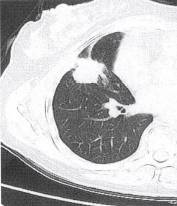

肝癌肺转移(3)肺部其他恶性肿瘤如肺原发肉瘤、肺癌肉瘤等。常症状轻微甚至无症状就诊时间 较晚,X线及CT表现为圆形、椭圆形肿块,边缘光滑,分叶多不明显,可为小切迹样或铸 型表现,直径多达6〜7cm,大者可占据一叶肺甚至一侧胸腔(图4)。增强肿块呈不规则

明显强化,表面常有包膜或假包膜。极少有肺门纵隔淋巴结转移。 医学百科网 | YxBaike.Com